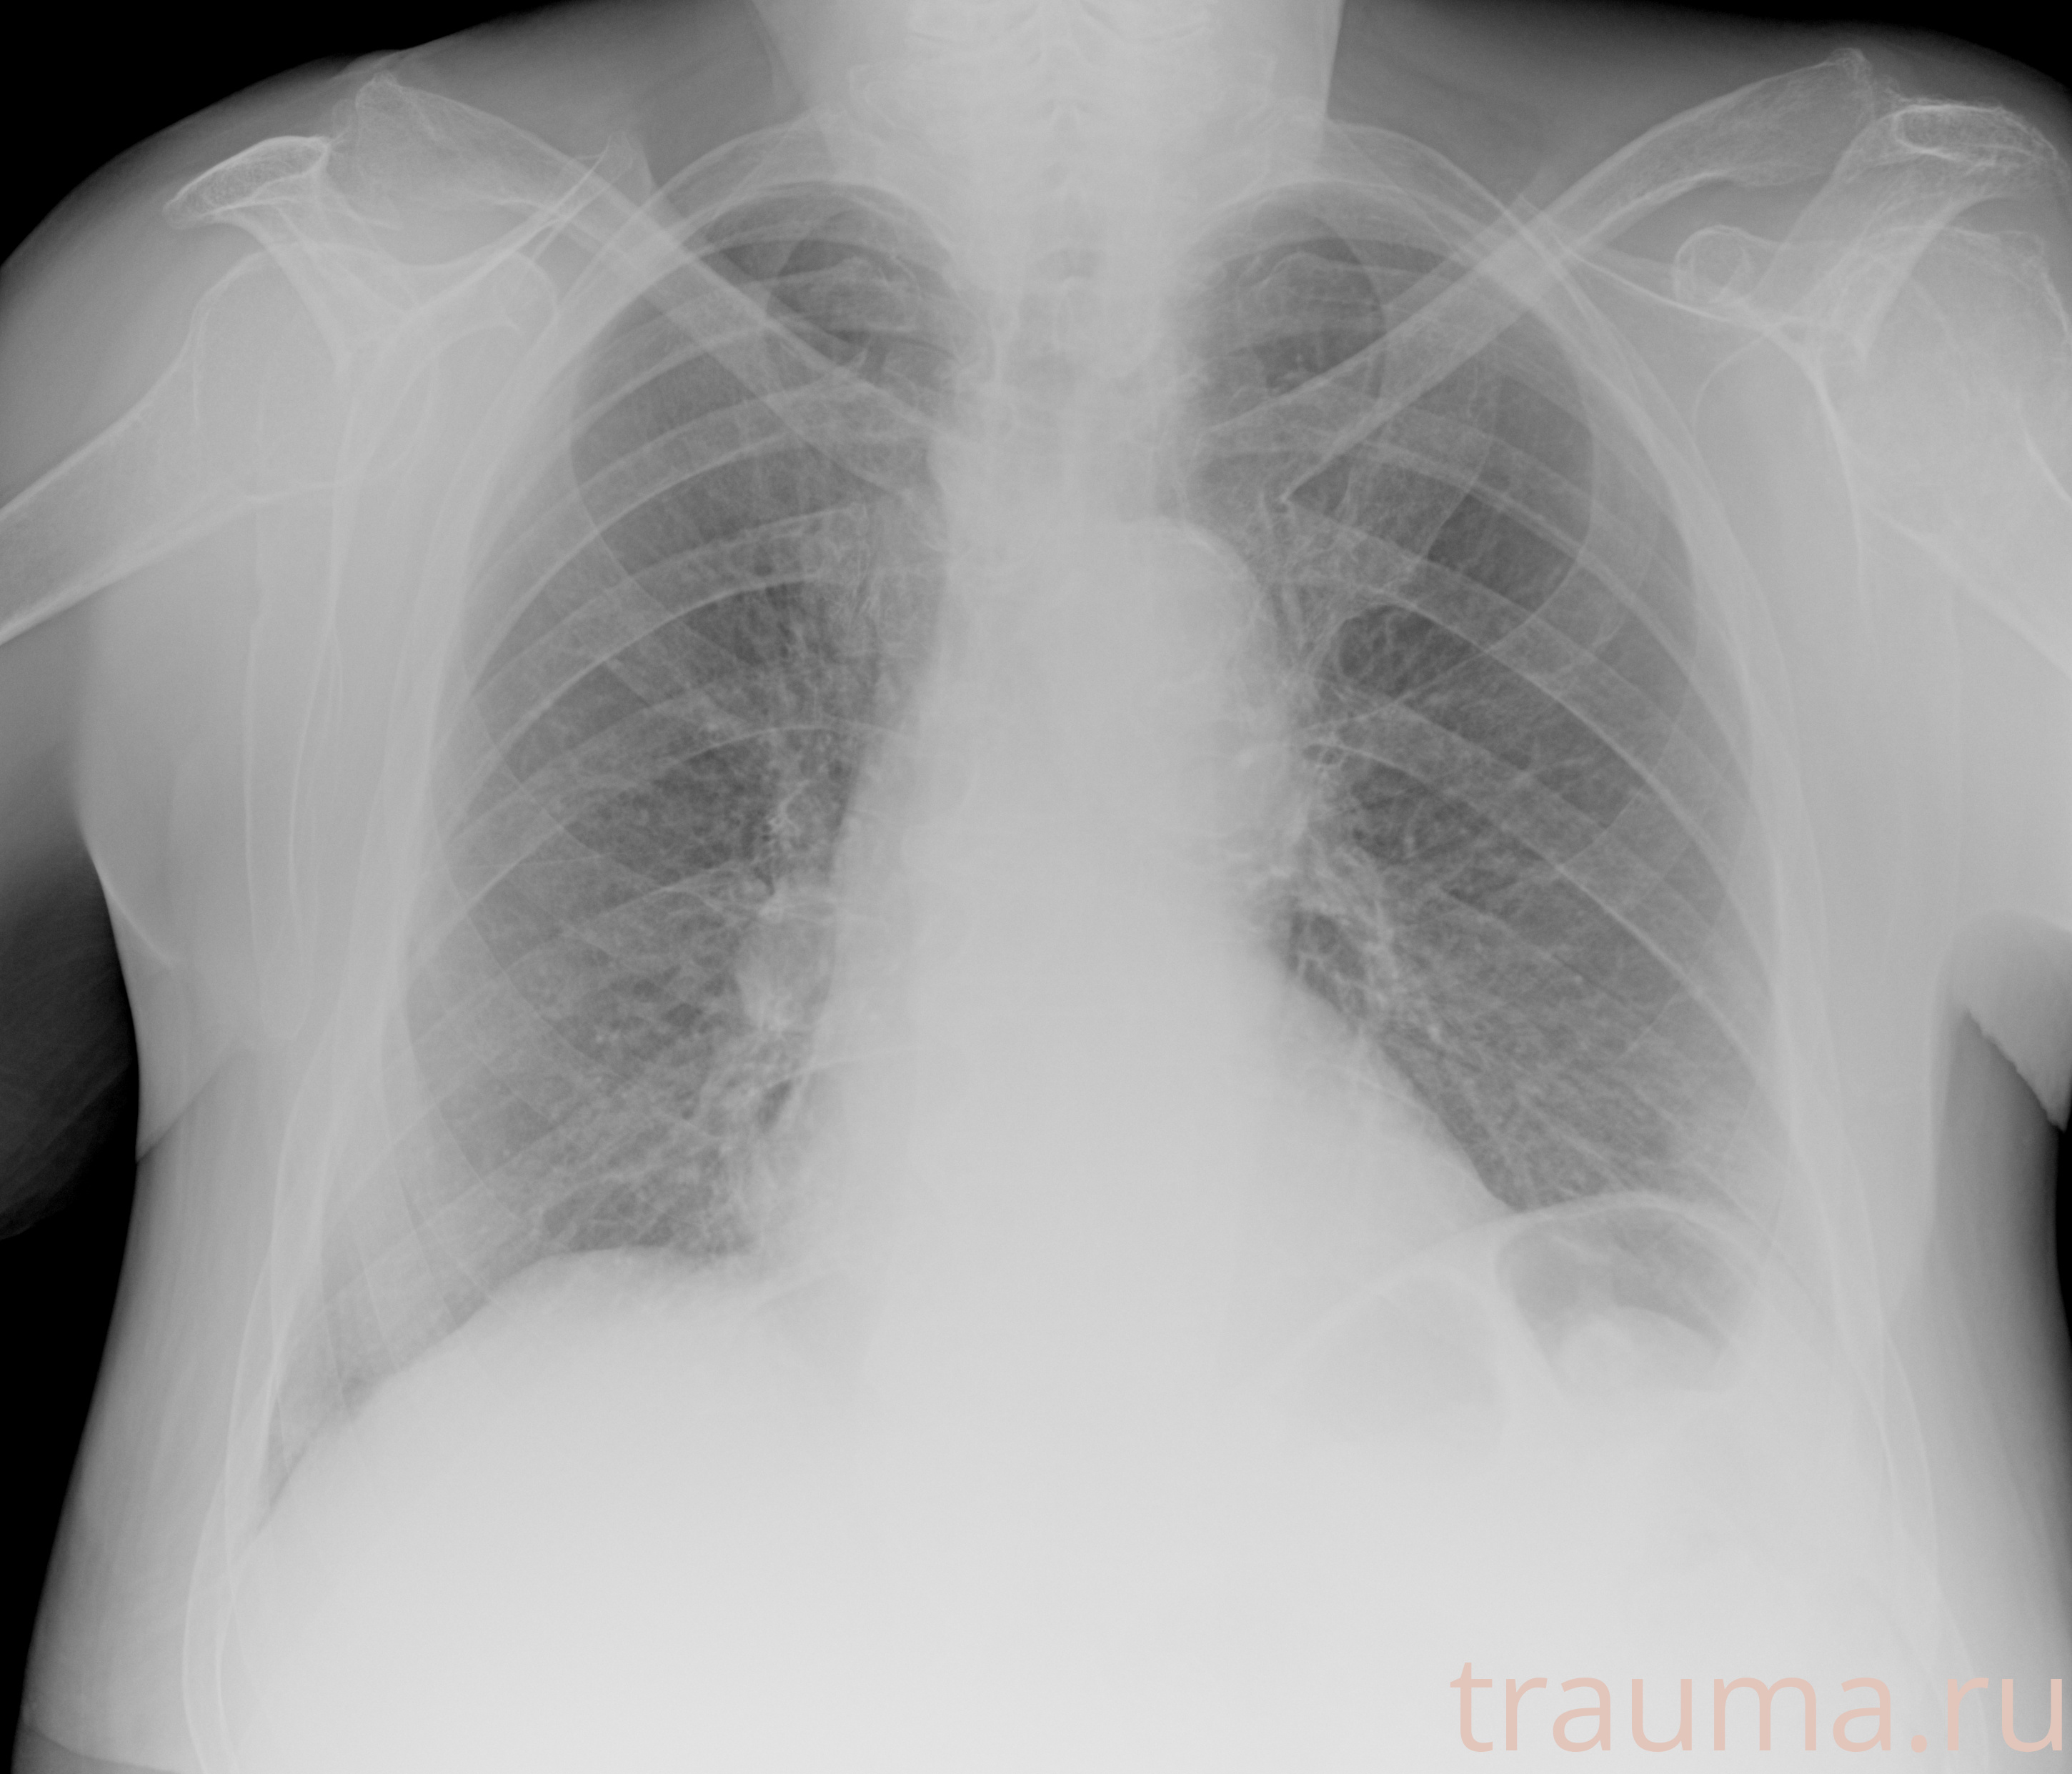

Рентгенограммы

Рентген на дому: по вашему адресу приезжает врач-рентгенолог, травматолог-ортопед с мобильным рентгеновским аппаратом, проводит диагностику травмы или заболевания, делает необходимые рентгенограммы, дает рекомендации по дальнейшему лечению. Получить качественные снимки в домашних условиях возможно благодаря уникальной методике, разработанной МосРентген Центром для института  Склифосовского